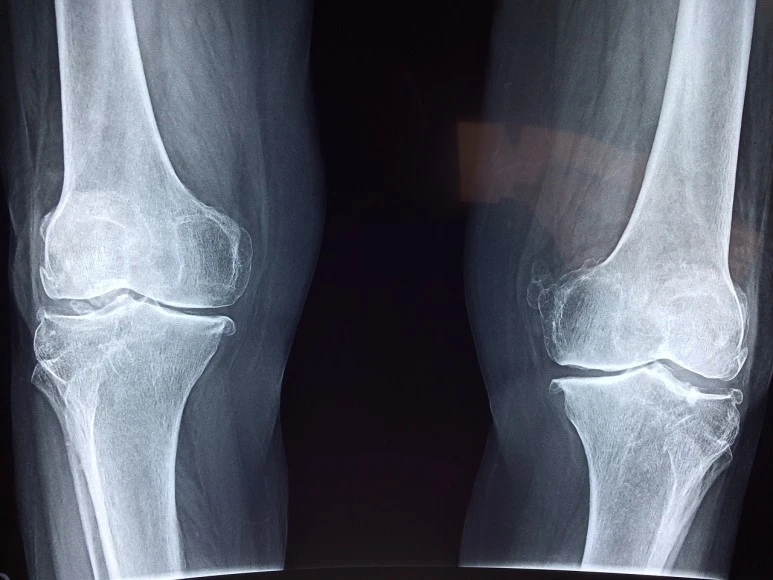

엑스레이 검사가 끝나고 다시 진단이 시작되었다.